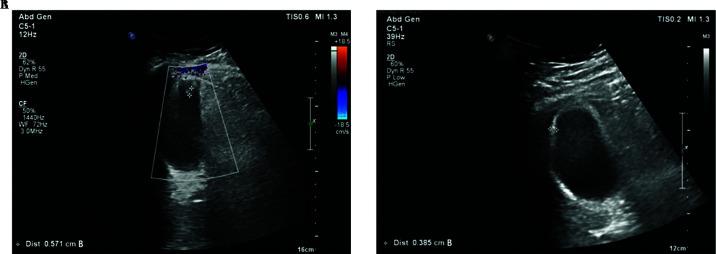

CASE/TECHNIQUE DESCRIPTION: A 30-year-old female presented with right upper quadrant abdominal pain for four days. The pain was radiating to the right shoulder, not related to fatty foods, associated with vomiting, anorexia, and burning micturition. On examination, she was vitally stable and afebrile with soft nondistended abdomen, a negative Murphy's sign, right lower quadrant rebound tenderness, and suprapubic tenderness. Laboratory tests showed leukocytosis (17.59 × 10) and high ALT (40 IU/L) and AST (32.5 IU/L). Ultrasound showed a distended gallbladder with two echogenic intraluminal nonshadowing echogenicity, the largest measuring 0.57 cm. Due to the vague presentation we elected to go for computed tomography of the abdomen which showed a distended gallbladder with adjacent fat stranding, subhepatic appendix with distended tip and no surrounding fat stranding. She underwent diagnostic laparoscopy with cholecystectomy and appendectomy. The patient had an uneventful postoperative course and was discharge home on day 1.

病例/技术描述:一名30岁女性因右上腹疼痛4天前来就诊。疼痛向右肩部放射,与油腻食物无关,伴有呕吐、厌食和尿痛。检查时,她生命体征平稳,无发热,腹部柔软无膨隆,墨菲氏征阴性,右下腹有反跳痛,耻骨上有压痛。实验室检查显示白细胞增多(17.59×10),谷丙转氨酶(ALT)升高(40 IU/L),谷草转氨酶(AST)升高(32.5 IU/L)。超声显示胆囊增大,腔内有两个无回声的强回声团,最大直径为0.57 cm。由于临床表现不明确,我们选择进行腹部计算机断层扫描,结果显示胆囊增大,周围脂肪有渗出,肝下阑尾尖端增大,周围无脂肪渗出。她接受了诊断性腹腔镜胆囊切除术和阑尾切除术。患者术后恢复顺利,术后第1天出院。